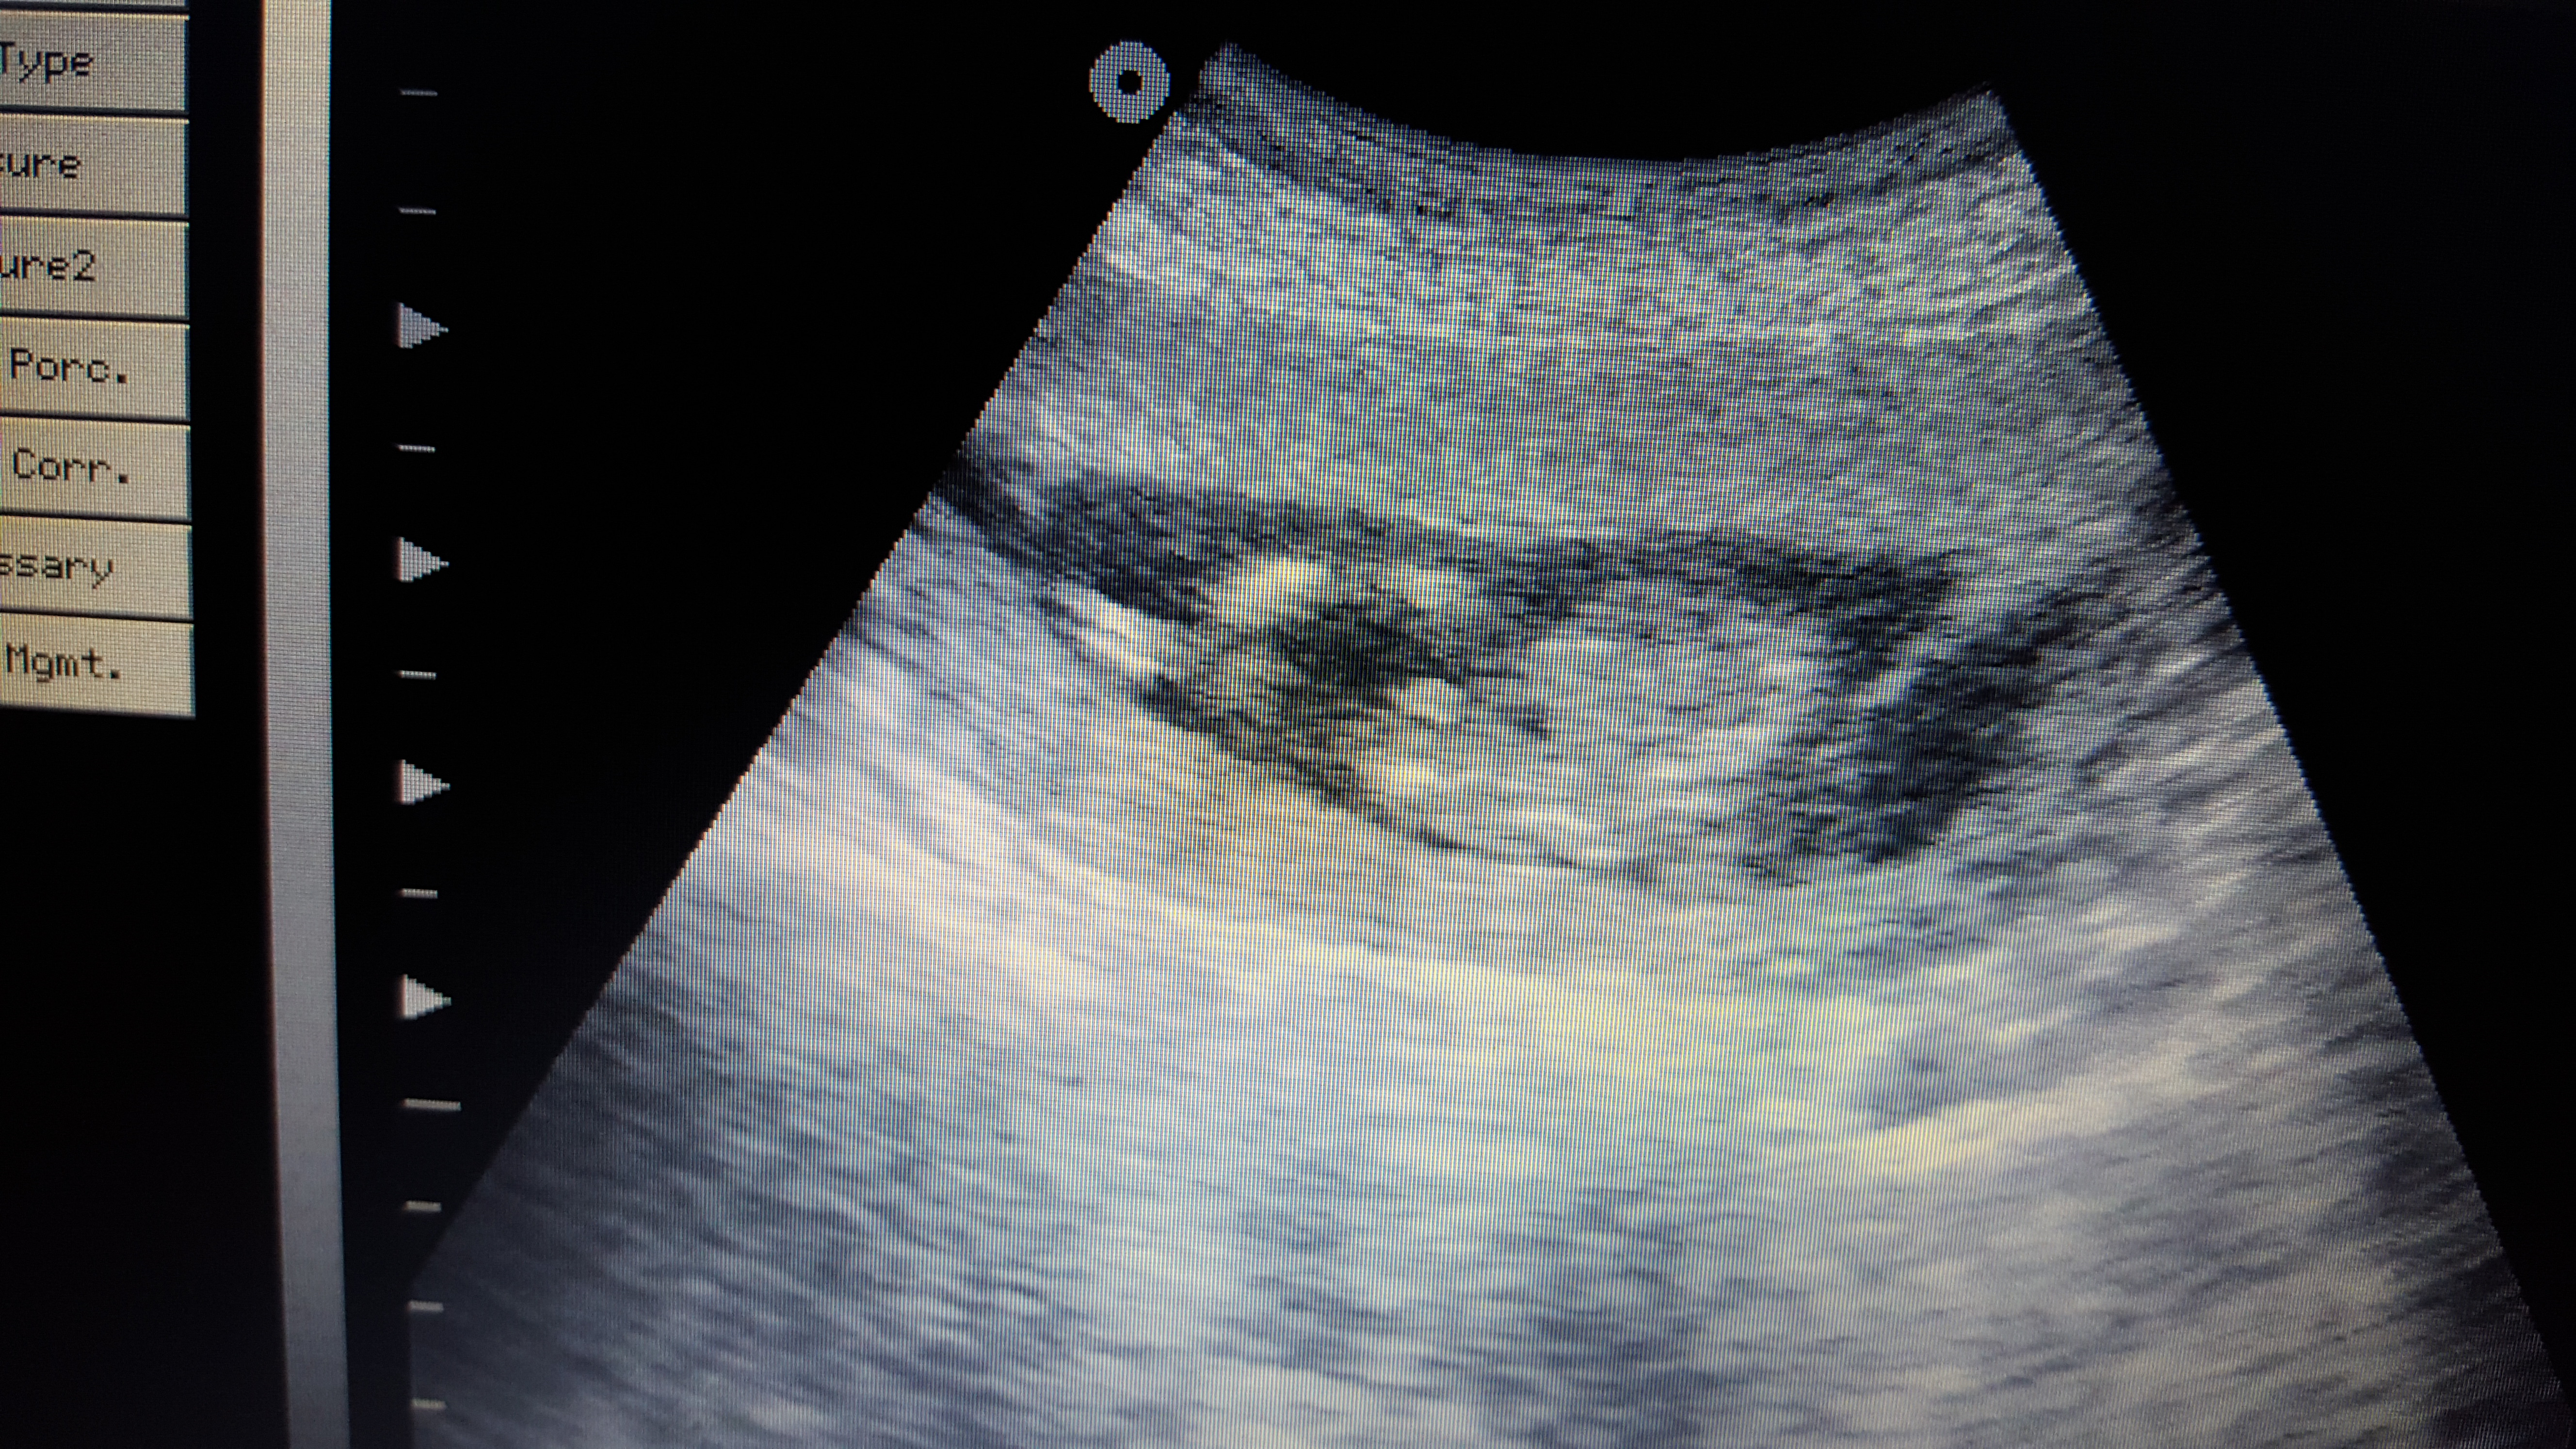

I'll add as many photos as possible to give an idea, photos aren't super clear but the 'protrusion' seems to be shrinking would you still guess blue?

14+4 Tech made no guess

Pictures are rather blurry but I'd guess boy.

Maybe boy?

boy lean

At 14 weeks I'd hazard a guess at boy but rather grainy to say for sure x

Leaning boy xx